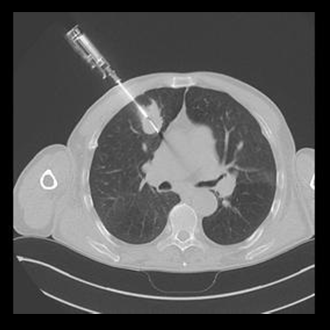

BIOPSY

Biopsy and Drainage

1. CT/USG guided biopsies.

2. CT/USG guided drainages.